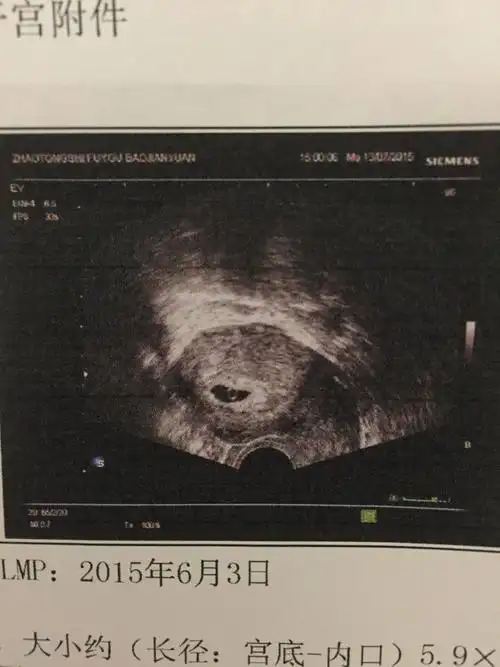

有图,介意者深慎入 药流后排出的孕囊从形状上能看出男女吗?排出可

怀孕44天,流了4天血,大家看看这个是孕囊吗?

请问怀孕十周,孕囊应该有多大?

药流出来的孕囊图片

孕7周的孕囊照片,看看是男宝还是女宝啊

流出来的孕囊是怎样的(有图慎入)